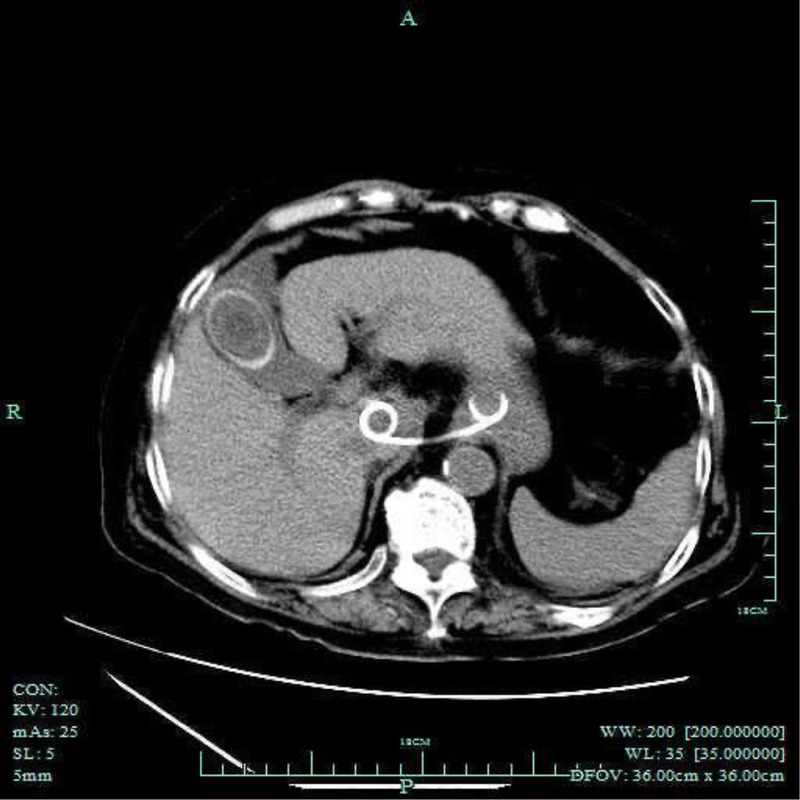

EUS-guided drainage of multidrug-resistant enterococcal caudate lobe abscess inaccessible with percutaneous approach (with video).